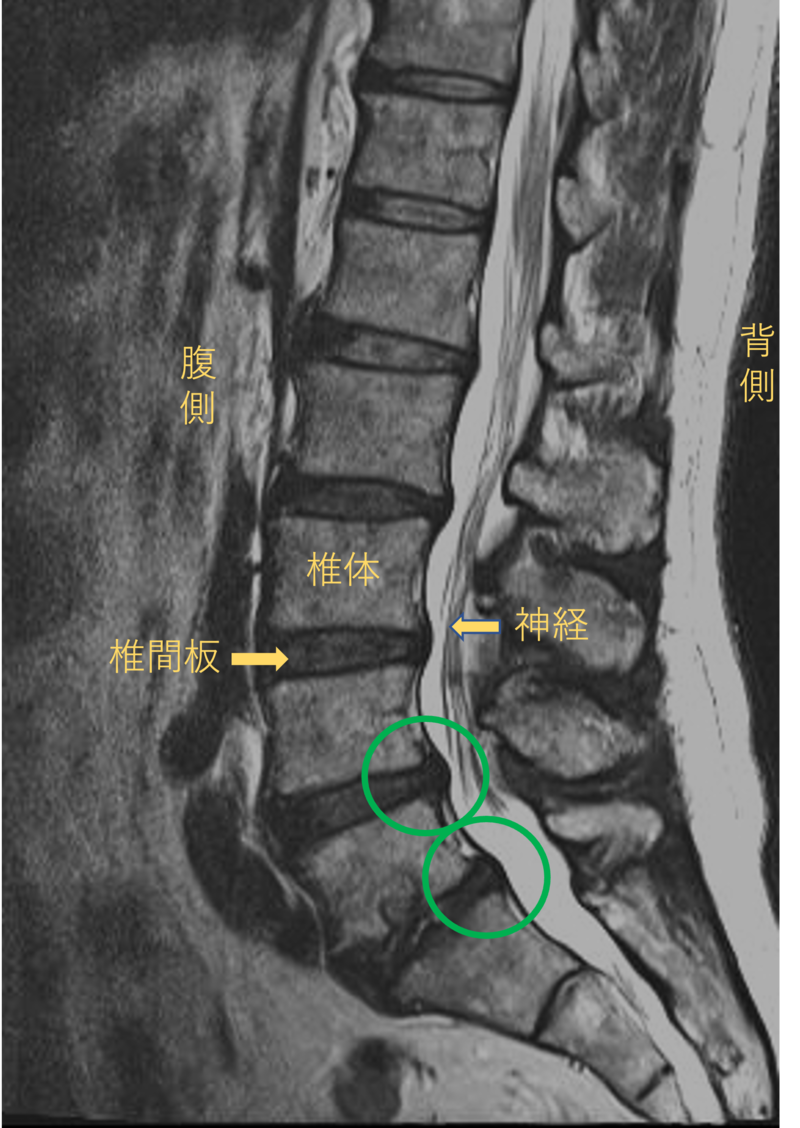

腰を横から見たMRI画像です。

腰椎という骨と骨の間に椎間板と呼ばれるクッションがあります。

このクッションの中身が飛び出す状態が椎間板ヘルニアと呼ばれます。

このMRI画像では、椎間板が背中側に飛び出して足に向かう神経が圧迫されることが痛み、しびれの原因となっておりました。